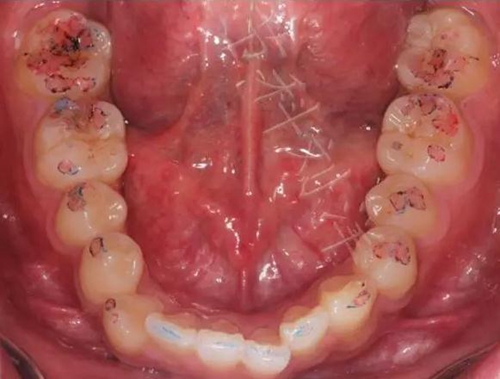

② 然后換用40微米紅色咬合紙,牙尖交錯位咬合

▲圖7:40µm咬合紙

▲圖8:40µm 正中咬合